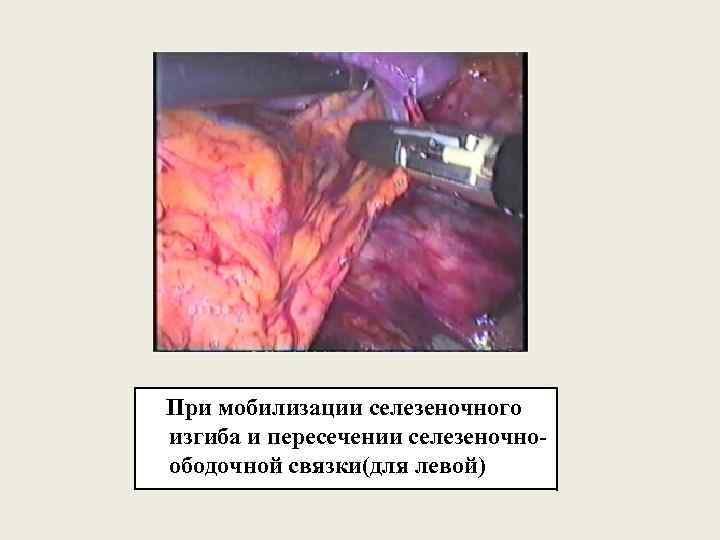

При мобилизации селезеночного изгиба и пересечении селезеночноободочной связки(для левой)